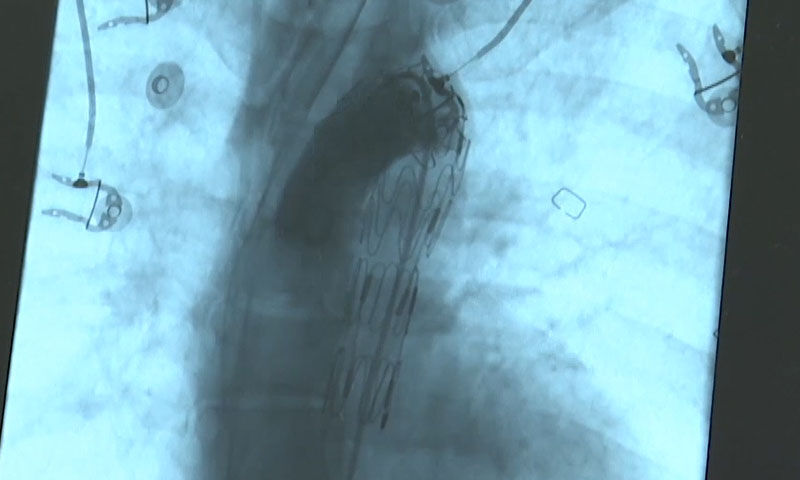

"Hastayı taburcu etmeden önce kontrol için endoskopisini yapmak istedik. Endoskopi yapılacağı gün hastamız kendini iyi hissetmediğini söyledi. Ağızdan çoklu kanaması oldu, acil şartlarda ameliyata aldık. Bu kadar büyük bir kanamanın şah damarı dediğimiz aorttan yemek borusuna oluşan irtibattan kaynaklı olabileceğini düşündük ve tahminimiz doğru çıktı. Hastamızda binde bir olabilecek komplikasyon meydana geldi. Şah damarından yemek borusuna kanallaşma oluştu. Hastanın hayatını kurtarmak ve kanayan bölgenin kontrol altına alınması için kalp damar cerrahisi kliniğinden arkadaşlarımızın müdahalesiyle aort damarı içerisine stent uygulaması yapıldı. 40 günlük tedavinin ardından hastamız sağlığına kavuştu."